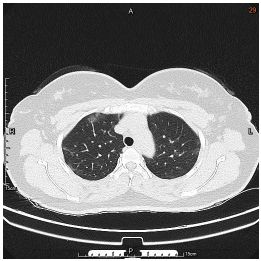

3. This 72-year-old diabetic man was taken to ER for productive cough for 10 days, and rapid progressive dyspnea for 2 days. He also had fever and chill for a week.